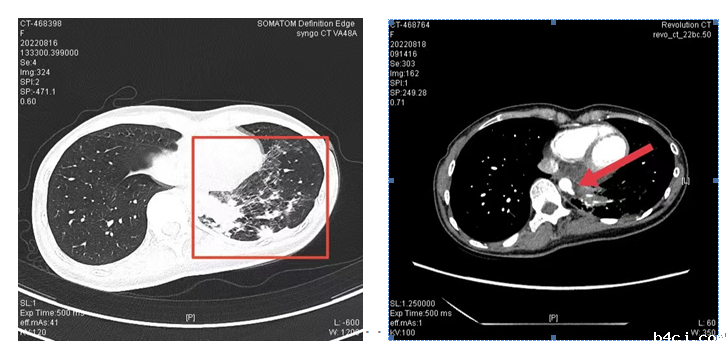

26岁的臧女士虽说体型消瘦,但觉得身体一向康健,平时没有任何基础疾病,近两年来却已是第三次肺部感染了。前两次咳嗽、发热都是到苏大附属医院就诊,门诊输液几日症状好转也就继续忙于工作了。这次又因为发热、咳嗽再次到苏大附属医院查胸部CT提示肺部感染,想着要好好治疗一番,就安排好了工作,和家人来到了离家近的我院呼吸与危重症医学科住院。第一次查房,呼吸与危重症医学科关键主任通过仔细阅片及询问患者既往就诊情况,考虑患者并非单纯的社区获得性肺炎,叮嘱尽快完善增强CT检查。通过增强CT发现患者左下肺为异常供血,明确诊断为肺隔离症。经过积极抗感染治疗,臧女士目前已康复出院,准备择期手术治疗。回访中,臧女士对我院医护人员赞不绝口。

肺隔离症,很多人都不太了解,这是一种少见的先天性肺部发育畸形,常与正常肺分开存在,有单独体循环血液供应,多有反复发作或持续存在的肺部感染性症状,增强CT结合三维血管重建发现异常供血可以确诊。